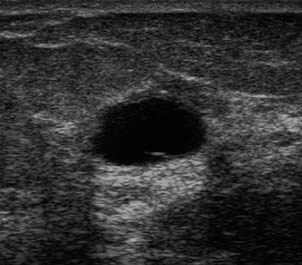

The target dataset was developed from 35 breast ultrasound scans that were segmented by an image-processing expert with extensive experience in breast lesion segmentation (the second author). The images, collected from the Web, are of different dimensions, ranging from to pixels (Figure 3, images resized for sake of illustration). These are the same images used to introduce EFIS originally [1].

Ultrasound images are generally difficult to segment, primarily due to the presence of speckle noise and low level of local contrast. It should be noted that the segmentation of ultrasound actually does require a complete processing chain, (including proper preprocessing and post-processing steps). However, the purpose of using these images was solely to demonstrate that the accuracy of the segmentation can be increased with the application of SC-EFIS.